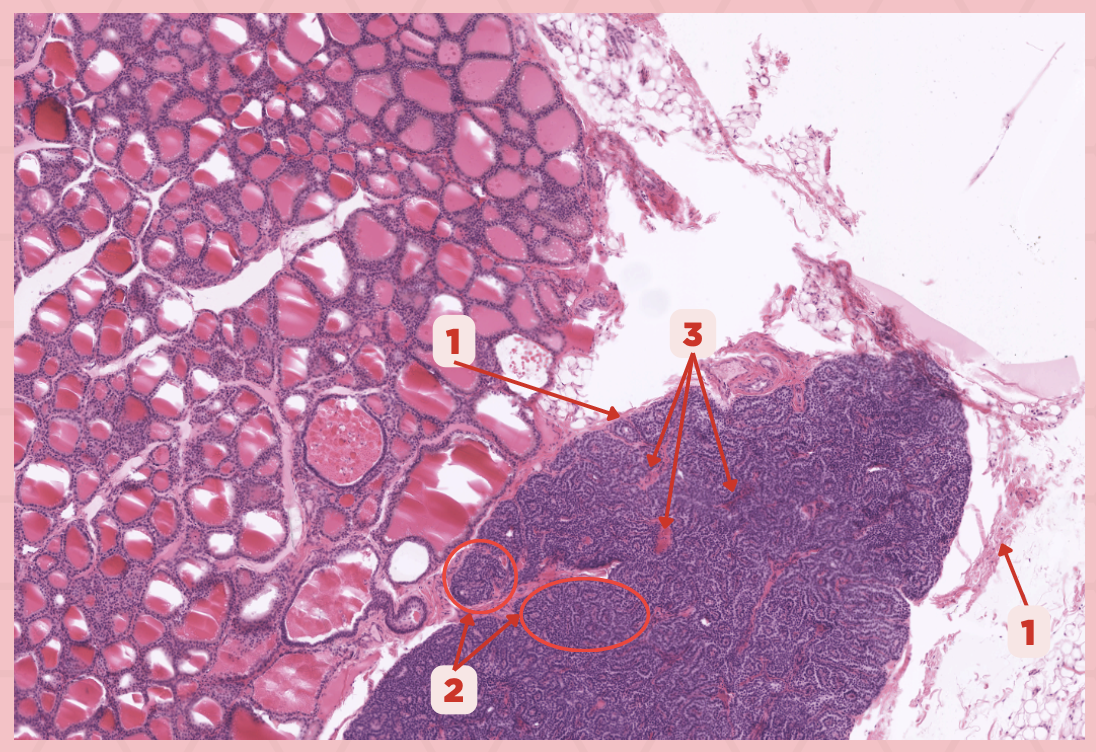

Thyroid-Parathyroid

Identify the specimen.

Thyroid Gland

Identify the structure labeled as 1.

Capsule

Identify the structure labeled as 2 and 4.

Parathyroid Gland

Identify the structure labeled as 3.

The parathyroid gland is divided into _____, packed with epithelial cells that form cords and clusters.

False

TRUE or FALSE. The parathyroid gland is only enveloped by its own thin connective tissue capsule.

Parathyroid Capsule

Identify the structure labeled as 1.

Lobules

Identify the structure labeled as 2.

Septa

Identify the structure labeled as 3.

Parathyroid

Identify the specimen.